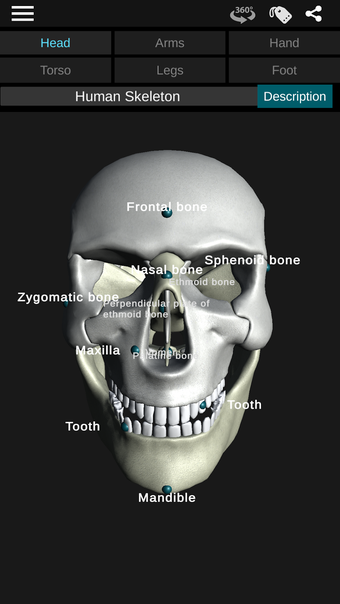

Osseous System in 3D Anatomy is a science educational application that gives basic information about human anatomy. A detailed and realistic skeleton model is available in 3D.

Through a series of educational exercises, users can learn to identify different bones and the location of each in the body.

By selecting one of the bones in the model, users can explore its form, location, and identification. In addition, users can move, rotate, and zoom the model to better understand its shape and location in the body. There are descriptions of different bones in the body, such as the skull, jaw, scapula, femur, tibia, pelvis, humerus, sternum, and vertebrae.